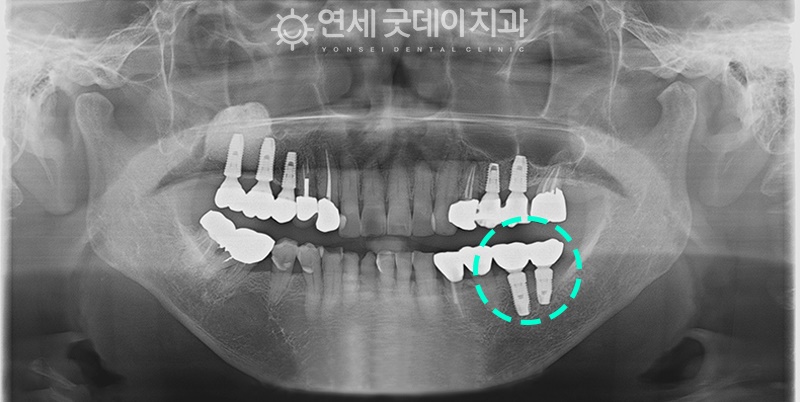

치료 후 18년경과

(2023년 3월 - 연세굿데이치과 검진자료)

18년이 지난 이후에도

왼쪽 아래어금니에 식립해드린 임플란트를

아주 잘 사용하고 계셨습니다.

이후 5개의 임플란트가 추가로 식립되었고

모두 덴티움 제품으로 심어드렸습니다.

(* 덴티움은 초기고정값이 좋아 치과의사 선호도가 높은 국산제품)

환자분께서는 긴 시간이 지났음에도

염증이 있거나 잇몸에 이상이 따로 발견되지 않고

거의 반영구적으로 잘 사용할 수 있도록

관리해주어 고맙다는 인사말씀을 전해주셨답니다.😊